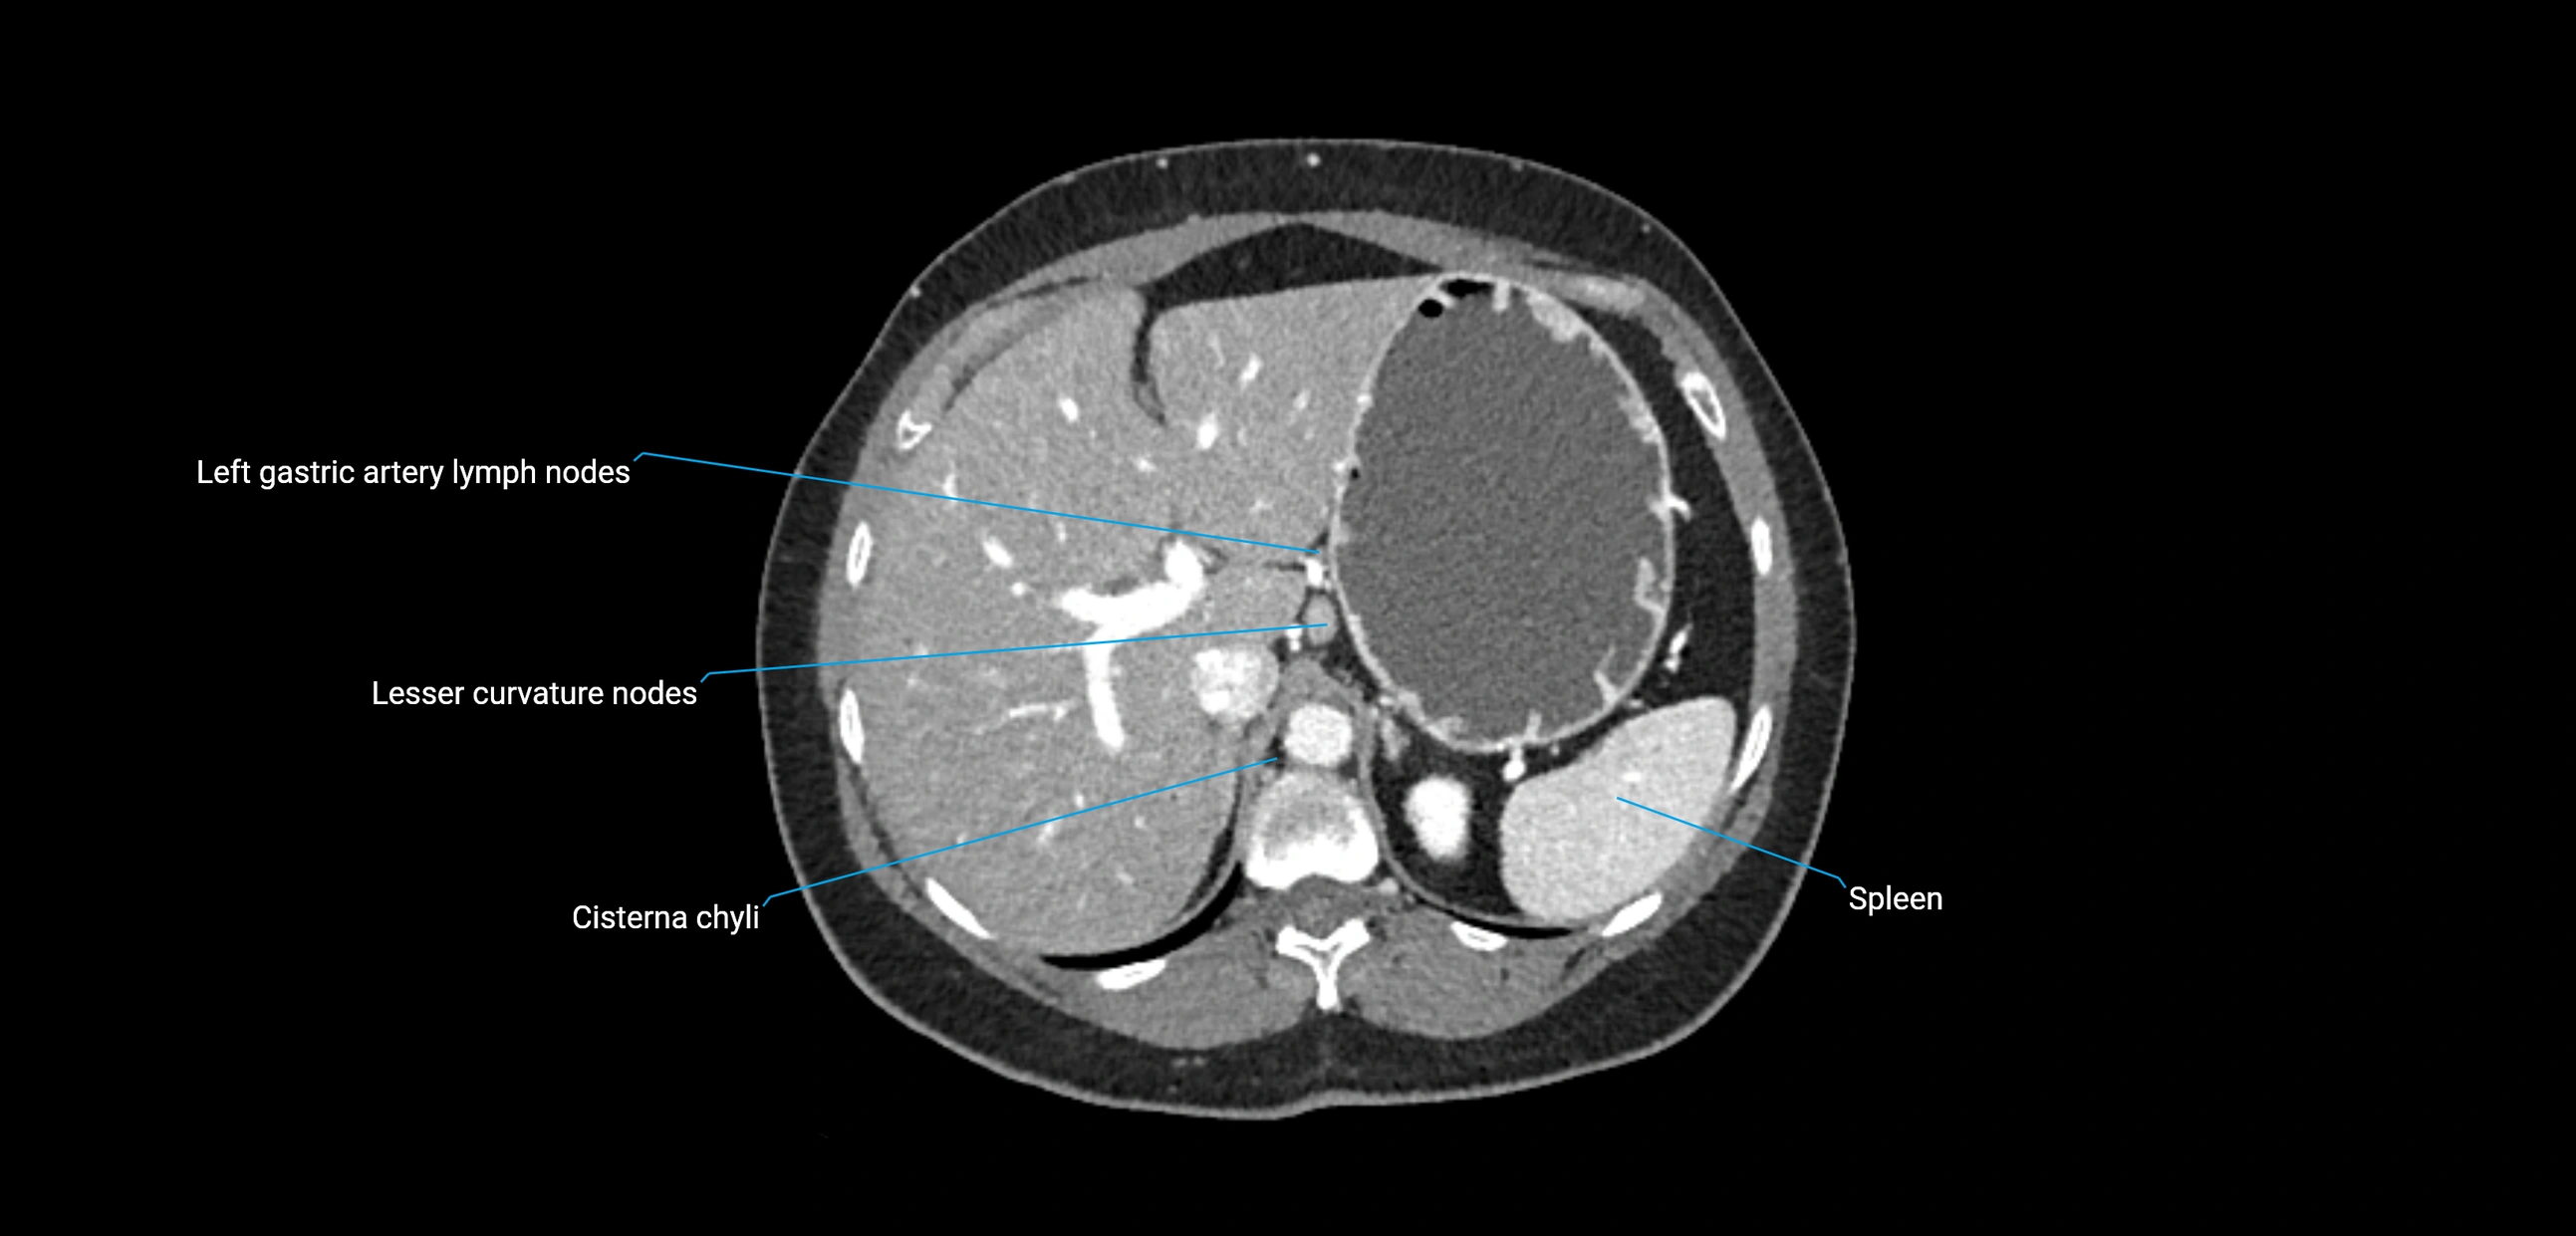

CT Appearance

CT Pre-Contrast:

• Nodes appear as soft-tissue density nodules adjacent to the aorta and IVC

• Calcification may be seen in chronic infections (e.g., tuberculosis)

CT Post-Contrast:

• Normal nodes enhance homogeneously

• Malignant nodes may show heterogeneous enhancement, central necrosis, or conglomerate formation

• Size >1 cm short axis is suspicious, though morphology and distribution are equally important